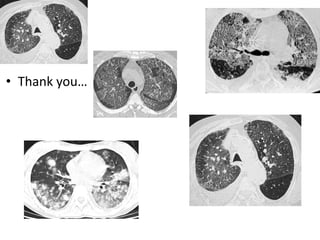

To Conclude…

• Thank you…

HRCT chest Ground glass opacities